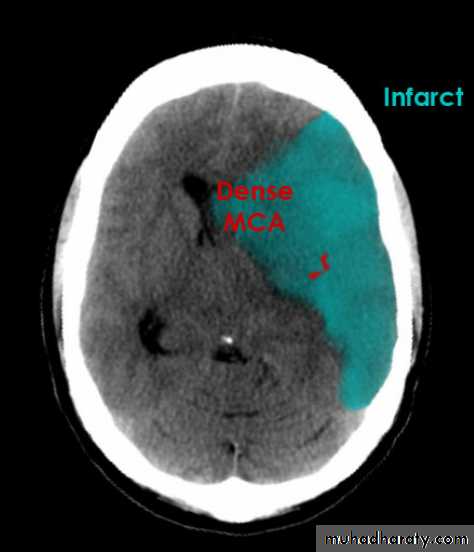

Acute infarction

History: sudden onset of hemiplegia , with slurred speech .

CT features:

Wedge shape area of hypo density involve the tributaries of anterior , middle or posterior cerebral arteries , ( i.e. priato frontal &priato occipital area )

Shift of the midline to the other side .

Compression of the ipsi lateral aspect of the regional ventricle by the edema

Dense middle artery sign

* wedge shape hypo density area.* Shifting of the midline & frontal horn